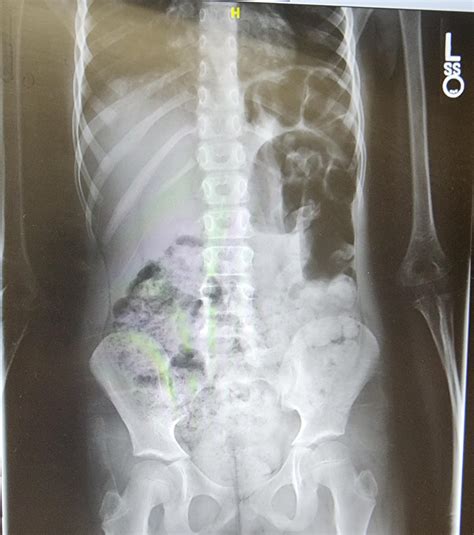

Interpreting Constipation in X-Ray

When interpreting an abdominal X-ray for constipation, radiologists look for several key indicators:

• Fecal Loading: The presence of a large amount of fecal matter in the colon.

• Colonic Dilatation: An enlarged colon, which may indicate chronic constipation.

• Air-Fluid Levels: The presence of air and fluid in the colon, which can suggest obstruction or slow transit.

These findings can help healthcare providers determine the severity of constipation and identify any underlying issues that may be contributing to the condition.